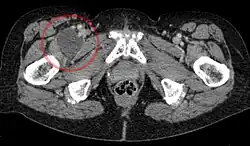

![]() Enlarged iliopectineal bursa in CT - scan | |

The iliopectineal bursa or the iliopsoas bursa is a large synovial bursa that separates the external surface of the hip joint capsule from the tendon of the iliopsoas muscle.[1]

The most proximal of part the iliopectineal bursa lies on the iliopubic eminence of the superior pubic ramus. The iliopectineal bursa passes across the front of the capsule of the hip joint and extends distally downwards almost as far as the lesser trochanter.[2]

The iliopectineal bursa frequently communicates by a circular aperture with the cavity of the hip joint.[1]